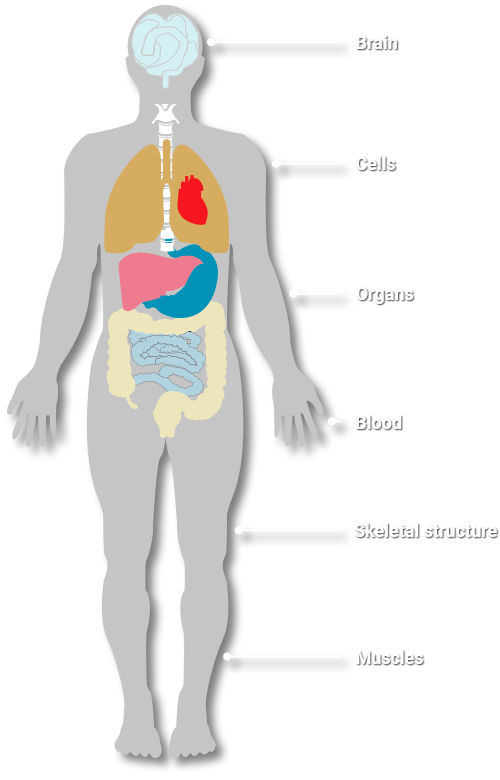

We understand that the onset of decline and disease is often caused by disruptions and disturbances within our system. These disturbances can lead to cellular breakdown, resulting in malfunction and degradation. Our mission is to assist you in mitigating, reducing, and ultimately eliminating the risks associated with cellular damage, enabling you to maintain optimal health and vitality.